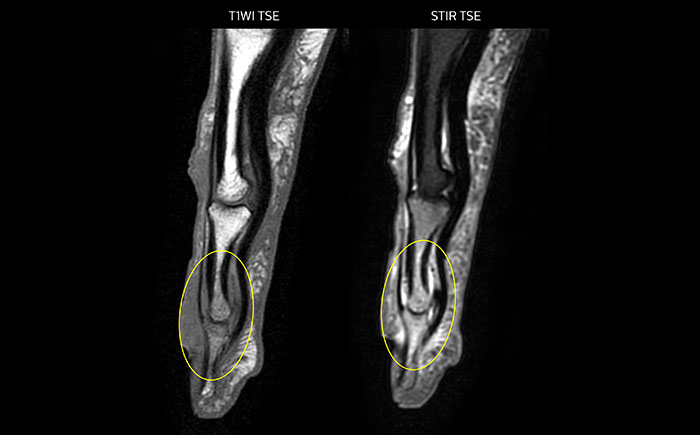

MRI examination on Prodiva 1.5T of a 72-year-old female with a malignant melanoma in the ankle. mDIXON TSE provides excellent fat suppression, without the distortion that is often seen at such extremities.

Prodiva imaging of the hand covers the fingertips and includes the full wrist as well. The dS MSK M coil is easy to use.

Scan time 2:55 min, FOV 160 mm, acq voxels 0.55 x 0.83 x 3.0 mm.

Scan time 4:19 min, FOV 160 mm, acq voxels 0.55 x 0.80 x 3.0 mm.